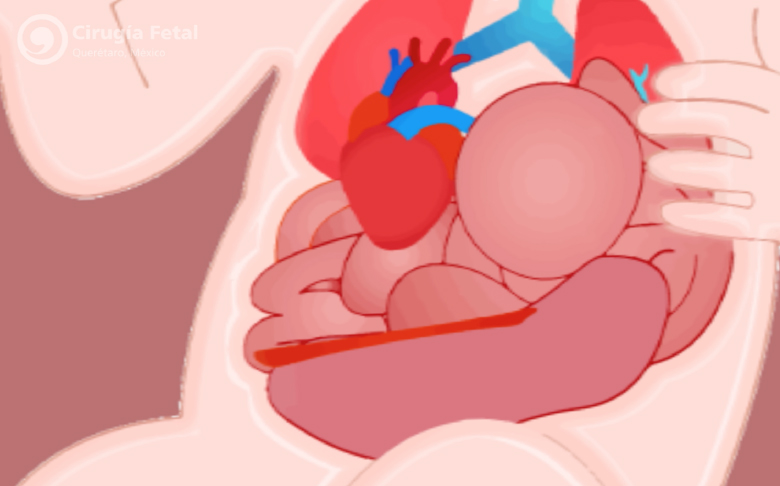

Al estar comunicados el tórax y el abdomen, las vísceras de este (intestino, estómago, bazo y en ocasiones el hígado) suben al tórax provocando una compresión de ambos pulmones que impide su adecuado crecimiento y maduración. Al nacimiento (momento en que el bebé utiliza por primera vez sus pulmones para respirar y adquirir oxígeno) los pulmones pueden ser tan pequeños en algunos casos que el bebé presente la muerte inmediata por asfixia e hipertensión pulmonar.

Su objetivo no es reparar el defecto del diafragma sino aumentar el desarrollo, crecimiento y maduración de los pulmones antes del nacimiento para mejorar las probabilidades de sobrevivir disminuyendo el riesgo de asfixia e hipertensión pulmonar al nacer.La cirugía es de mínima invasión y se realiza con anestesia local a la madre y anestesia intramuscular al feto. Se hace un corte menor de 5mm en el abdomen de la madre, se introduce un fetoscopio dentro del útero y bajo visión directa y sin realizar ningún corte al feto, se introduce el fetoscopio a través de la boca fetal hasta entrar a su tráquea donde se coloca y se infla un balón. Este se deja inflado en la tráquea del feto de 2 a 6 semanas para ser retirado antes de su nacimiento.